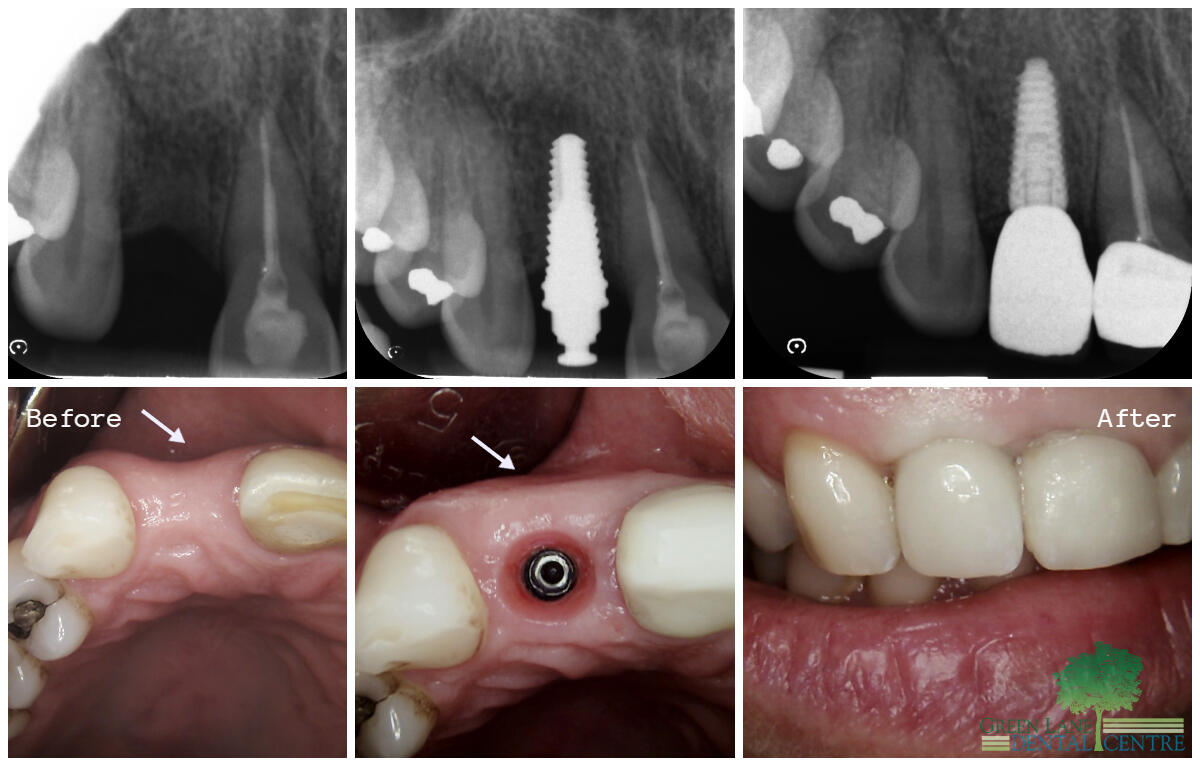

Smile Gallery